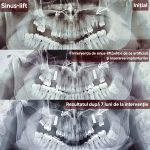

Cea mai răspândită intervenție de augmentare osoasă în stomatologie este operația de sinus lift (ridicarea sinusului) – o procedură chirurgicală de adiție osoasă realizată la maxilarul superior pentru a crește volumul osos necesar inserării implanturilor dentare. Prin ridicarea membranei sinusale și introducerea unui material de grefare, se creează o bază solidă, fiind necesară când sinusurile sunt prea coborâte sau osul este prea subțire. Scopul acestei proceduri este crearea unui suport stabil pentru implanturi dentare în zona laterală superioară (molari/premolari). Procedura de adiție osoasă se efectuează sub anestezie locală. Vindecarea durează de obicei între 4 și 6 luni.

Implantarea și ridicarea sinusurilor permit restabilirea zâmbetului estetic chiar și în cazurile extrem de dificile, adică și în situațiile când pacientul se adresează tardiv. Înainte de apariția acestei tehnici, unii pacienți trebuiau să se mulțumească doar cu proteze și punți mobilizabile. Odată apărută posibilitatea creșterii osoase, contraindicațiile pentru instalarea implantelor au fost considerabil reduse.